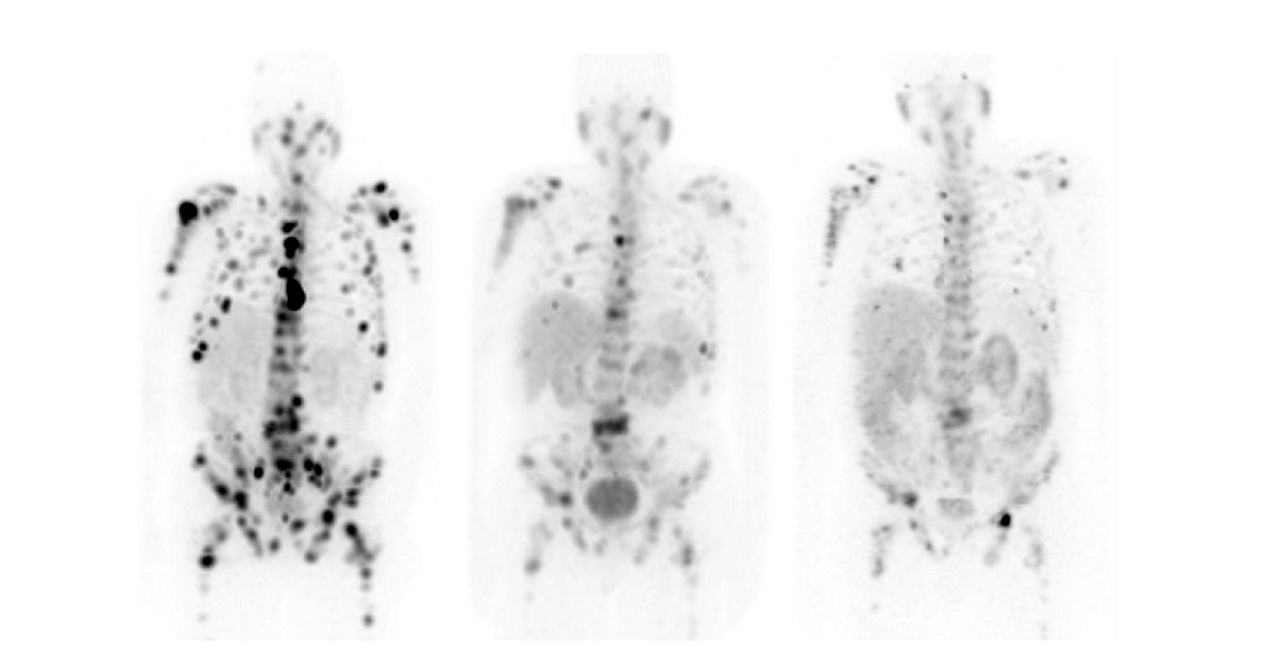

The approach of zeroing in on tumor receptors with positron- and gamma-emitting radioligands to visualize cancer cells, and beta- or alpha-emitting radioligands to destroy cancer cells makes theranostics the quintessential targeted care pathway.

Radioligand therapies have historically been one of the last treatments for cancer, but new evidence shows positive results if this type of care is used earlier, closer to when cancer is diagnosed.² Because of the limited side effects of this precision treatment, it is now a pre-chemo therapy option for some patients.

Already chosen to treat patients with mCRPC, neuroendocrine tumors, thyroid and other cancers, researchers are exploring⁵ a wider range of cancers, such as brain, breast, pancreatic, and ovarian, that may be treatable with radioligand therapies in the next five to ten years.

Radionuclides like ¹⁷⁷Lu, ¹³¹I, and ⁹⁰Y have established themselves as effective cancer treatments.⁶ In the next few years, researchers are working to add several more radionuclides to the fight against cancers, including two alpha-emitting candidates, ²¹²Pb and ²²⁵Ac.⁵

Hundreds of clinical trials⁵ are well underway to explore the efficacy of radioligand therapy in battling many cancers. About a tenth of those trials are already in the late stages.